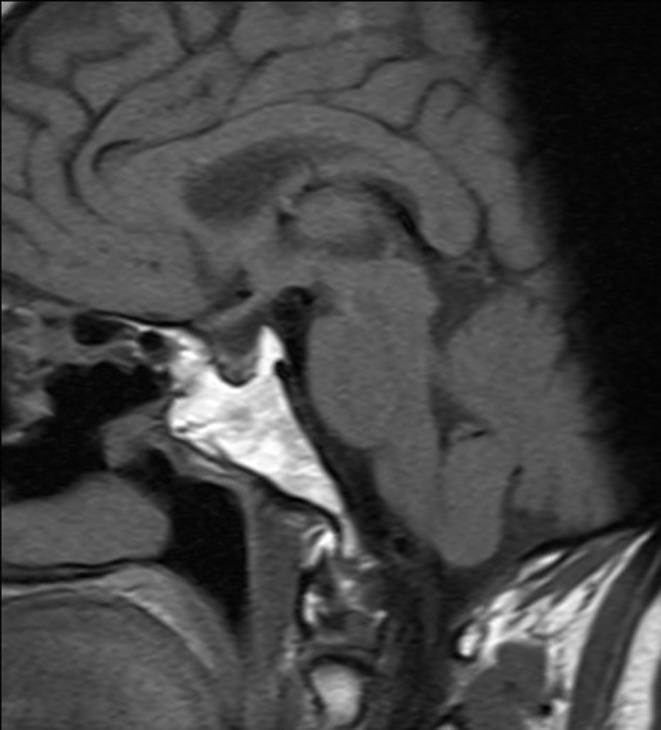

Figure 1.

MRI, June 22, 2010. Sagittal cut.

In September 2001, treatment with somatostatin analogues (slow-release (SR) lanreotide (30 mg)) was started (one injection every 14 days) to reduce symptomatology. However, due to insufficient disease control, the dosing frequency was increased in February 2002 to one injection every 10 days. Jointly, the Departments of Neurosurgery and Endocrinology decided to perform a second transsphenoidal neurosurgery (September, 2002). Pathological findings showed an eosinophilic, sparsely granulated adenoma, with a low Ki67 index. A postoperative MRI revealed tumour remnants mainly located in the right lobe, with invasion of the right cavernous sinus. After surgery, a 75 g oral glucose tolerance test (OGTT) was performed. The baseline GH was 8 ng/mL and GH nadir was 12 ng/dL. Based on these OGTT results, the patient was diagnosed with active postoperative acromegaly. In March 2003, treatment with subcutaneous injection lanreotide (Somatuline Autogel) was started (120 mg every 56 days). Doses were adjusted in accordance with changes in the GH and IGF-1 levels, which steadily decreased over time until both had normalized by January 2005 (random GH <1 ng/mL and normal IGF-1 levels) (see Table 1 for detailed measurements). The patient did not receive oestrogen replacement therapy during treatment. A pituitary MRI performed in June 2012 showed postsurgical changes, including only minimal remains of the gland, retraction of the optic chiasm (Figs 1 and 2) and no evidence of any remaining residual tumour.